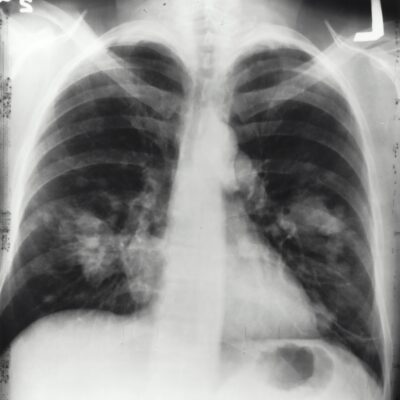

Lung cancer

Lung cancer occurs when cells divide in the lungs uncontrollably, causing tumours to grow. This can affect a patient’s breathing and the cancer can spread to other parts of the body.